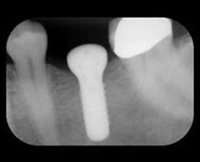

X-Rays and impressions (molds) are taken of the jaw and teeth to determine bone, gum tissue, and spacing available for an implant. While the area is numb, the implant will be surgically placed into the bone and allowed to heal and integrate itself onto the bone for up to six months. Depending on the type of implant, a second surgery may be required in order to place the "post" that will hold the artificial tooth in place. With other implants the post and anchor are already attached and placed at the same time.

After several weeks of healing the artificial teeth are made and fitted to the post portion of the anchor. Because several fittings may be required, this step may take one to two months to complete. After a healing period, the artificial teeth are securely attached to the implant, providing excellent stability and comfort to the patient.